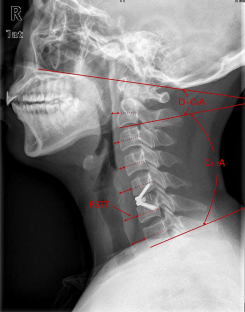

Fig. 2